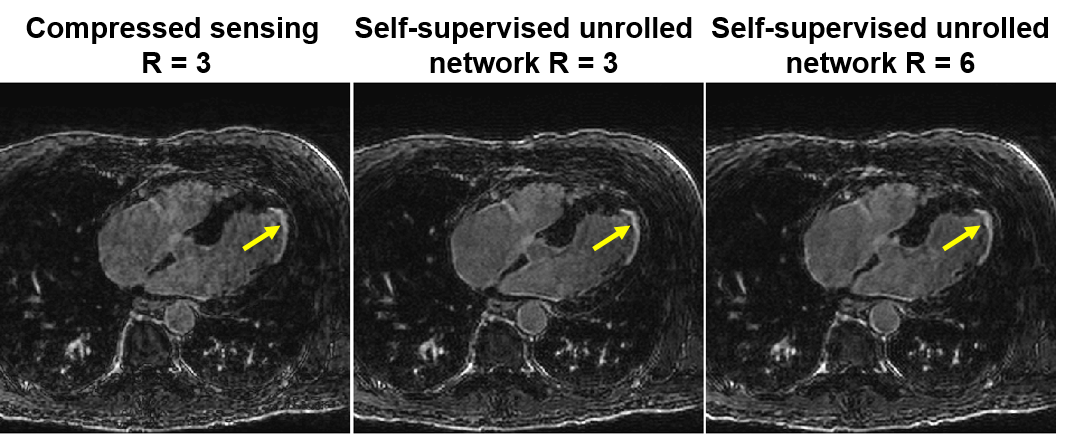

Finally, as aforementioned the need for fully-sampled data for training had hindered the use of deep learning reconstructions for certain applications. Thus, alternative methods have been explored. Dynamic contrast-enhanced MRI (DCE-MRI) represents one such challenging acquisition, where -space data is acquired continuously while contrast agent been injected to the patient. The dynamic distribution of the contrast agent causes the image contrast dynamics, hence, both the -space and image are time-series. In this setting, a variational network was trained on simulated data with radial -space trajectories, as fully sampled dataset with both high spatial and temporal resolution was infeasible to acquire [81]. With the recent advances outlined in Section III-D1, training in such scenarios can also be done in with more realistic datasets without resorting to simulations. For instance, in another contrast-based cardiac acquisition, called late gadolinium enhancement imaging, unrolled networks have been trained using prospectively accelerated acquisitions without fully-sampled reference data [82], and were shown to improve on clinically used compressed sensing methods, doubling the achievable acceleration rates, as depicted in Figure 6.